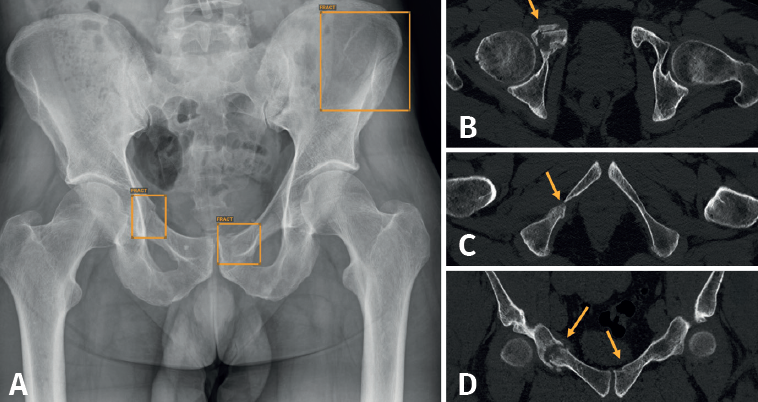

Aunque no hemos realizado un estudio de sensibilidad y especificidad por la complejidad que entraña en la práctica asistencial, consideramos que los resultados son satisfactorios, en línea con lo publicado en la literatura científica. Destacamos la eficacia del algoritmo en la detección de pequeñas fracturas arrancamiento (Figura 3), fracturas de radio distal y proximal (Figura 4), y fracturas múltiples (Figura 5).